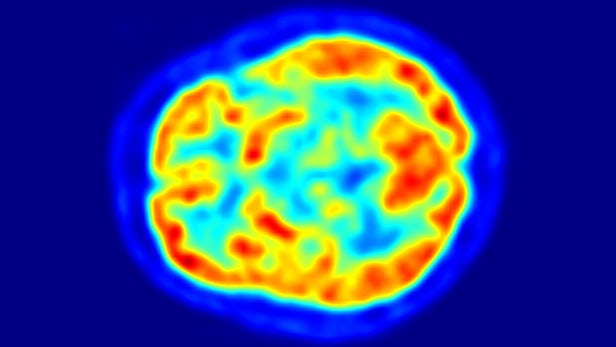

目前用于确定阿尔茨海默症发病的诊断工具之一是一种称为18-F-氟脱氧葡萄糖PET扫描(FDG-PET)的脑成像扫描。这种扫描传统上用于识别几种类型的癌症,但近年来证明它本身可用于识别阿尔茨海默症以及其他几种类型的痴呆症。

在最新的研究中,旧金山加利福尼亚大学的研究人员基于1002名患者的2100多幅FDG-PET脑图像上训练了机器学习算法,观察脑细胞新陈代谢的微小变化。AI先是在90%的图像上进行了训练,然后在剩余10%的图像以及来自40名从未研究过的患者的独立检查中进行算法性能验证。

“大脑中葡萄糖摄取模式的差异是非常微妙和分散的,”研究的共同作者、加州大学旧金山分校放射与生物医学成像系的Jae Ho Sohn说道,“人们善于发现特定疾病的生物标记物,但代谢变化代表了一个更全面和微妙的过程。”

虽然临床医生擅长FDG-PET脑图像评估,但新的深度学习技术能够识别密集成像数据中更微妙的模式。该算法能够预测所有进展为阿尔茨海默病的病例——具有82%的特异性和100% 敏感性,与放射科医师相比,诊断时间平均提前了75.8个月。Jae Ho Sohn表示,“我们对算法的性能非常满意,它能预测每一个进展为阿尔茨海默症的病例。”